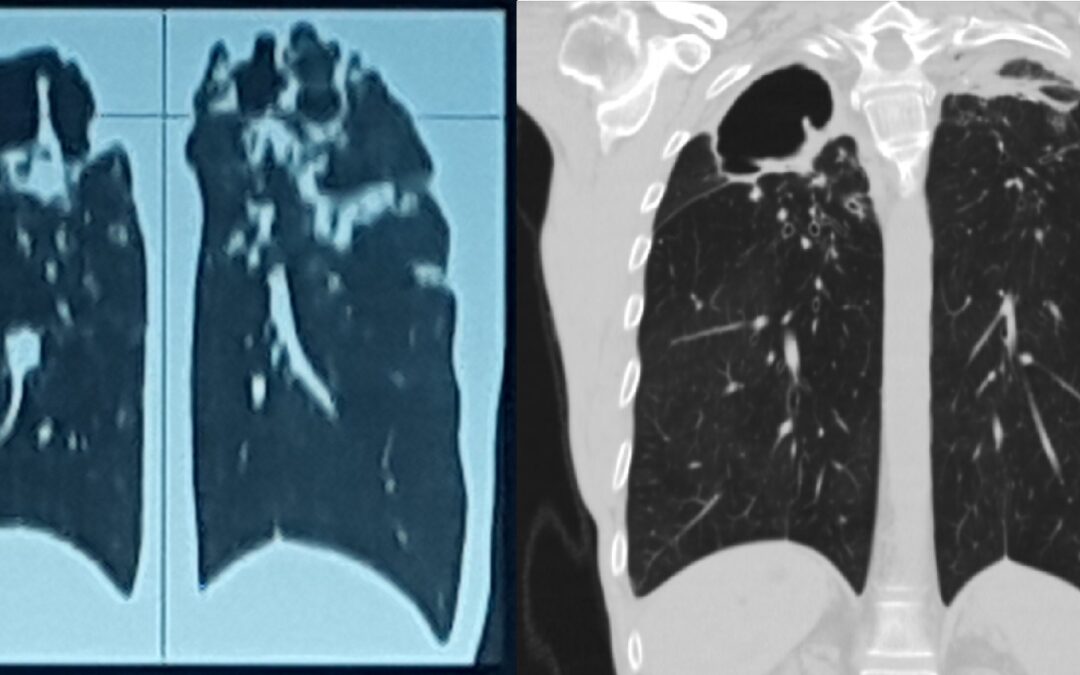

ფილტვის მოცულობის ბრონქოსკოპიული შემცირება ბულოზური ემფიზემის შემთხვევაში პაციენტი 42 წ მამაკაცი. აქტიური მწეველი. თავს ავად გრძნობს რამოდენიმე თვეა. ჩივილები: ძლიერი ქოშინი ფიზიკურ დატვირთვაზე, ჰაერის უკმარისობა, საერთო სისუსტე. გულმკერდის კტ კვლევით – ორივე...